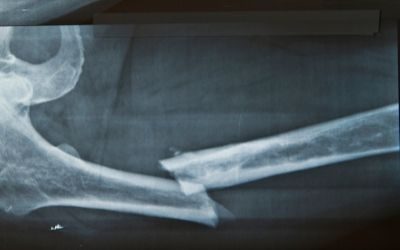

Erano in molti a ritenere che lo sviluppo dei vaccini contro il virus SARS-CoV-2 ad opera di aziende come BioNTech e Moderna avrebbe proiettato le terapie a RNA nel firmamento delle nuove tecnologie, dato l’ampio ventaglio di condizioni mediche a cui esse possono rivolgersi. E, infatti, lo studio pubblicato lo scorso febbraio dai ricercatori della Mayo Clinic (Stati Uniti) sulla rivista Science Advances conferma che la tecnologia dell’mRNA può trovare terreno fertile anche in settori diversi da quelli della virologia. Uno di questi è l’ortopedia dal momento che i dati dello studio citato confermano la validità di questo approccio nella rigenerazione dell’osso fratturato.